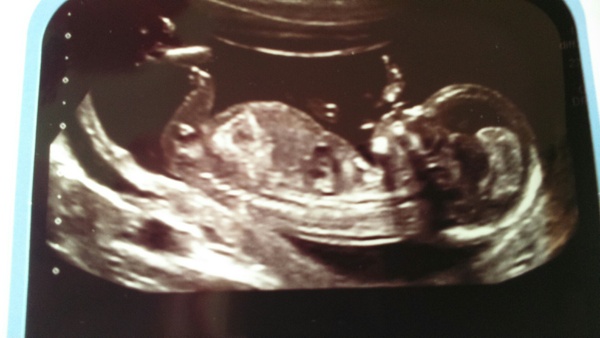

it's nice to hear about all the good scans. My nuchal test appointment isn't until next Friday and it feels like a loooooooong wait.